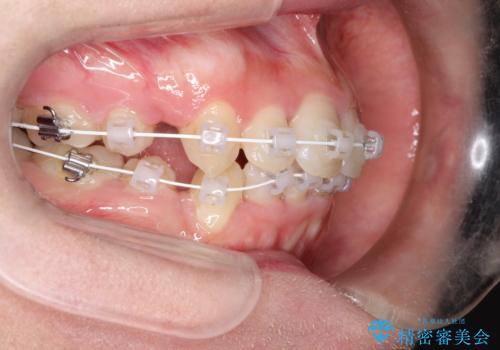

全体的ながたつき ワイヤーによる抜歯矯正で整った歯並びへ

- 上下の全体的ながたつきが気になるとのことで来院されました。

上下左右の前から4番目の歯を抜歯をして、ワイヤー矯正にて並べる計画としました。

患者様が装置を早期に除去したいという希望もあり、少々下の前歯のがたつきが残った状態で矯正を終了しました。

全体的ながたつきがなくなり、見た目の印象がよくなりました。